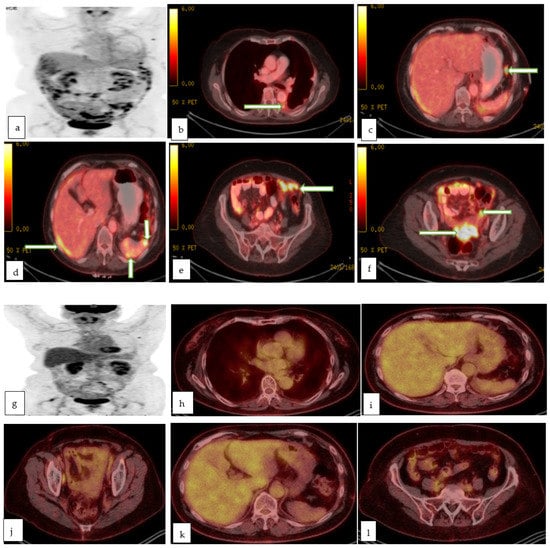

- FDG PET-CT is a modality of high specificity yet low sensitivity in delineating primary gynecologic malignancies with a well-established role in preoperative staging, monitoring therapy response, and detecting recurrence in all locally advanced gynecological malignancies. New tracers are introduced but with limited data in the literature, thus not routinely used in clinical practice.

4.5. Positron Emission Tomography-Computed Tomography (PET-CT)

4.6. PET-MRI

- Dejanovic, D.; Hansen, N.L.; Loft, A. PET/CT Variants and Pitfalls in Gynecological Cancers. Semin. Nucl. Med. 2021, 51, 593–610. [Google Scholar] [CrossRef] [PubMed]

- Narayanan, P.; Sahdev, A. The role of (18)F-FDG PET CT in common gynaecological malignancies. Br. J. Radiol. 2017, 90, 20170283. [Google Scholar] [CrossRef] [PubMed]

- Burger, I.A.; Vargas, H.A.; Donati, O.F.; Andikyan, V.; Sala, E.; Gonen, M.; Goldman, D.A.; Chi, D.S.; Schöder, H.; Hricak, H. The value of 18F-FDG PET/CT in recurrent gynecologic malignancies prior to pelvic exenteration. Gynecol. Oncol. 2013, 129, 586–592. [Google Scholar] [CrossRef] [PubMed]